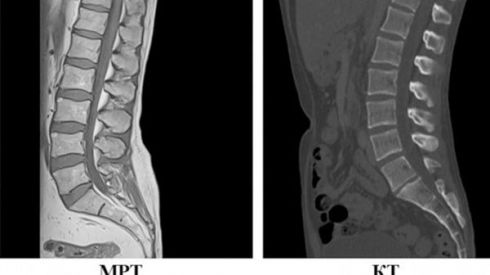

КТ і МРТ: у чому різниця?

Ціна МРТ вища за КТ і дає більш деталізовані, чіткі зображення. Але не можна однозначно сказати, що, наприклад, МРТ краще за КТ або навпаки. Доцільність того чи іншого дослідження визначає виключно лікар – усе залежить від того, що йому потрібно побачити.